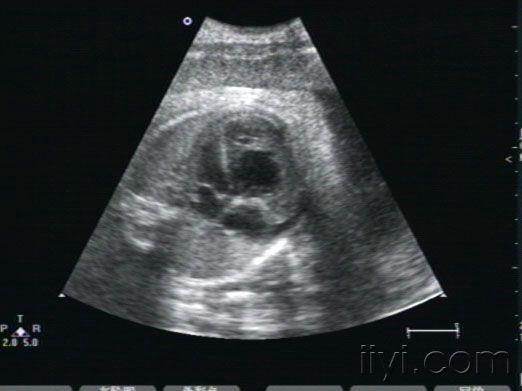

胎儿心包积液

• 孕38周,10天以前在多家医院检查胎儿正常。近一周来自觉腹胀,下坠。发现胎儿心包积液,并且右室壁好象很厚。胎儿生下来后,临床医生没有听到杂音,遗憾的是孩子也没来检查心脏。我们没有开展胎儿心脏,请各位专家帮忙看下,到底是什么原因,胎儿右室壁增厚考虑什么病,为什么生后没有杂音呢?